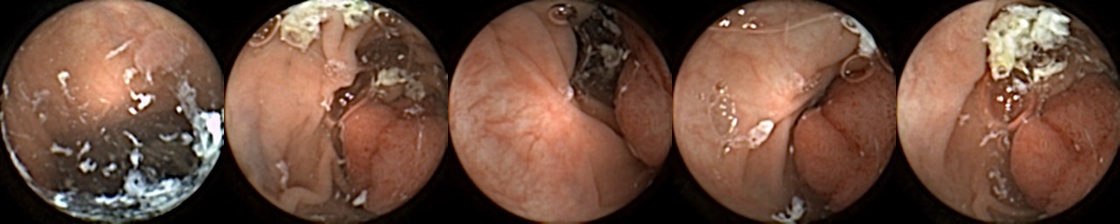

Refer to caption

Figure 1: Positive exemplar images with each row showing five images of a unique polyp, where in each row, the first image corresponds to first partial and fifth image is the last full view of the same polyp. The polyps have been marked in green for each image.

For MIV, we construct both positive and negative exemplar pairs from this multi-patient polyp image dataset. Positive exemplars are constructed based on the five images from a single polyp, with one of the second, third, or fourth image designated as the query and the remaining four images forming the target bag. Images from five example polyps are shown in Figure 1. Negative exemplars are constructed using a more sophisticated strategy: if a patient has multiple polyps, the query image is selected from one of those polyps at random, while target images are sampled from other polyps of the same patient; if a patient has only one polyp, target images are drawn from different patients entirely.